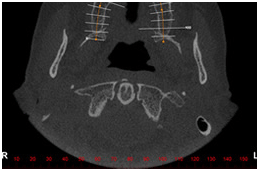

Todo exame tomográfico tem como ponto de partida uma imagem guia, composta por uma escala milimetrada. A escala milimetrada está localizada no bordo inferior da imagem e serve de orientação para localização dos cortes tomográficos transversais oblíquos que serão efetuados a partir da imagem guia.

Neste caso a imagem guia é um corte coronal (frontal), semelhante a uma radiografia panorâmica ou uma imagem axial com demarcações a cada 5mm.

TC Imagem guia panorâmica TC Imagem guia axial